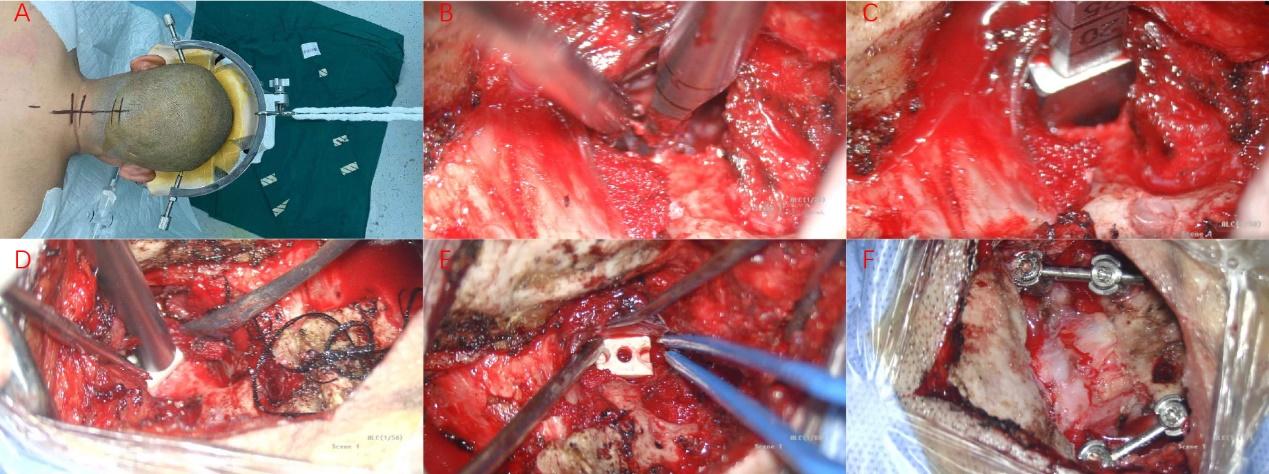

患者全麻成功后取俯卧位,头部保持中立位略后仰并牵引固定,标记枕颈部后正中长约10cm直切口,常规消毒铺巾和局麻后,依次切开皮肤、皮下组织和颈后肌肉,牵开器牵开,显露枕骨鳞部、寰枢椎至颈3的棘突和椎板,见寰枕融合,显微镜下显露双侧寰枢椎侧方关节,去除侧方关节内关节软骨并撑开,扩张侧方关节间隙,双侧侧方关节内各置入含人工骨的Cage1枚,双侧颈1-2分别置入椎弓根螺钉,取钛棒固定,然后磨钻磨除枕大孔后缘部分骨质,开窗约2*2cm,见寰枕后缘减压充分、硬膜膨隆明显,术腔彻底止血后放置引流管一根,依次关闭各层。手术经过顺利,术后患者清醒后安返病房。术后患者症状较术前明显好转。目前患者已顺利出院。

术中所见

A:手术体位、切口;B:破坏寰枢椎关节间软骨;C:寰枢椎关节间撑开并试模;D:置入Cage;E:Cage位置良好;F:置入椎弓根螺钉并钛棒固定,寰枕后缘减压充分。